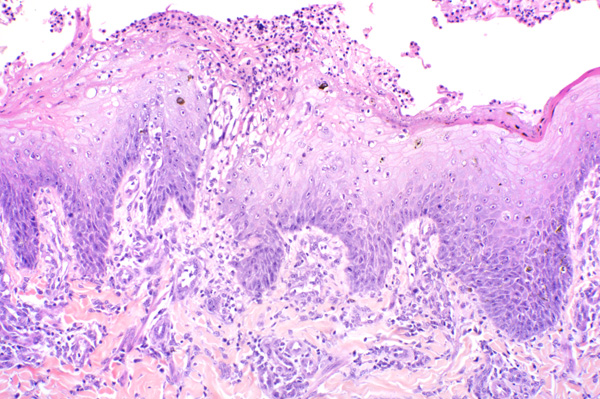

| 10x   |   Hematoxylin and Eosin | ||||

The epithelium is ulcerated and the dermis is infiltrated by inflammatory cells.